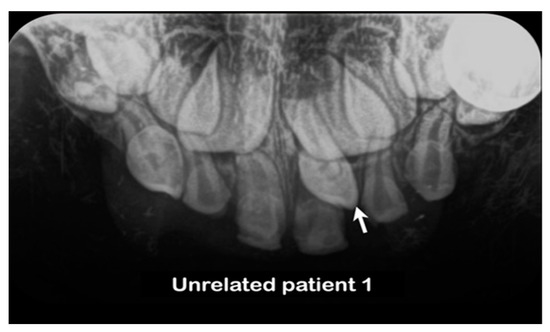

| Family 2 | Unrelated patient 1 | Thai | Female | Single mesiodens | Normal | Erupted | c.2248C>G p.Pro750Ala rs199549354 |